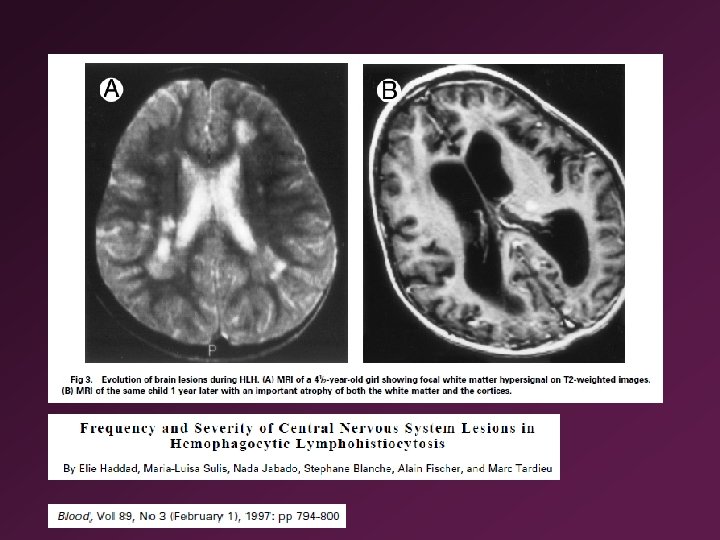

Some deficiencies can lead to lymphoproliferative diseases (Table 4. 1) • Familial hemophagocytic lymphohistiocytosis (FHL or FHLH) is caused by an inherited deficiency of perforin • Hemophagocytosis: ingestion of red blood cells by macrophages • Pfp-/- mice infected with some types of viruses result in a disease similar to FHL because the immune system is uncontrolled demonstrates that perforin plays an important role in regulating the immune response • Hemophagocytic lymphohistiocytosis (HLH) =Hemophagocytic syndrome (HPS) =Macrophage activation syndrome

• In FHL, mutations prevent NK cells and cytotoxic T cells from releasing their cytoplasmic granules, which leads to uncontrolled proliferation of lymphocytes and macrophages • These cells phagocytose blood cells and release huge amounts of proinflammatory cytokines • Cytokine burst explains the inflammation, fever and systemic illness • T cell and macrophage infiltration in liver, spleen, lymph nodes, bone marrow, and central nervous system • T cells and macrophages respond strongly to microbes to compensate for the CTL and NK cell defects?

• • • Anemia Thrombocytopenia Hemophagocytosis in bone marrow, spleen, lymph node Increased cytokine release: interferonγ, TNF, IL-6, IL-10, macrophage colony -stimulating factor (M-CSF) Treatment: control the cytokine burst by chemotherapy and immunotherapy with etoposide, corticosteroids and cyclosporine, followed by bone marrow transplantation